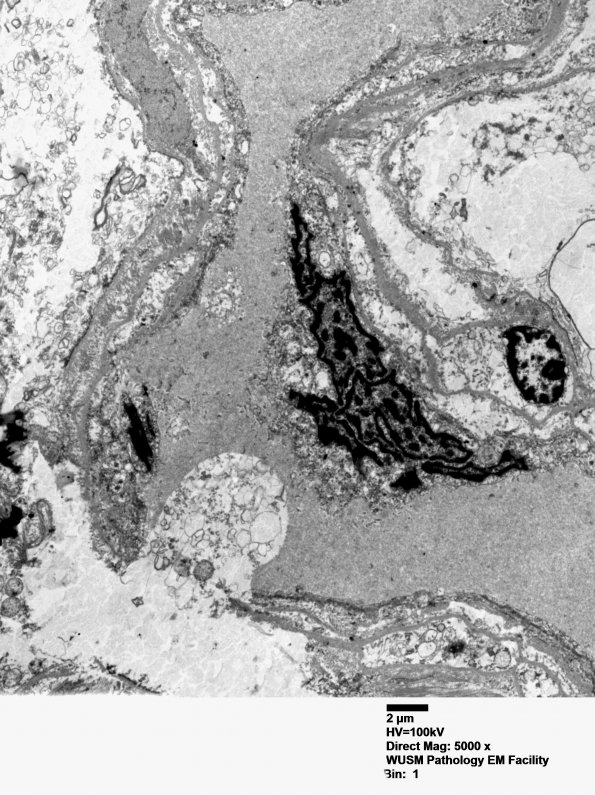

Washington University Experience | INFECTION | Bacteria | Mycoplasma | 1J1 Mycoplasma (Case 1) EM 006 - Copy

1J1-9 Ultrastructural Neuropathology ---- 1J1-3 Progressively higher magnification images of the multilobated cell. (Electron micrograph)